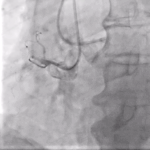

Διάνοιξη Χρονίων Ολικών Αποφράξεων (CTO)

διάνοιξη ολικών αποφράξεων

Η διάνοιξη χρόνιων ολικών αποφράξεων αποτελεί μία από τις πιο απαιτητικές και εξειδικευμένες παρεμβάσεις στον τομέα της επεμβατικής καρδιολογίας. Αναφέρεται στην προσπάθεια αποκατάστασης της αιματικής ροής στεφανιαίων αρτηριών που έχουν πλήρως αποφραχθεί για διάστημα μεγαλύτερο των τριών μηνών.

Παρά τις τεχνικές δυσκολίες, οι σύγχρονες τεχνικές και η εμπειρία των εξειδικευμένων καρδιολόγων έχουν αυξήσει σημαντικά τα ποσοστά επιτυχίας, προσφέροντας ανακούφιση από τα συμπτώματα και βελτίωση της καρδιακής λειτουργίας.